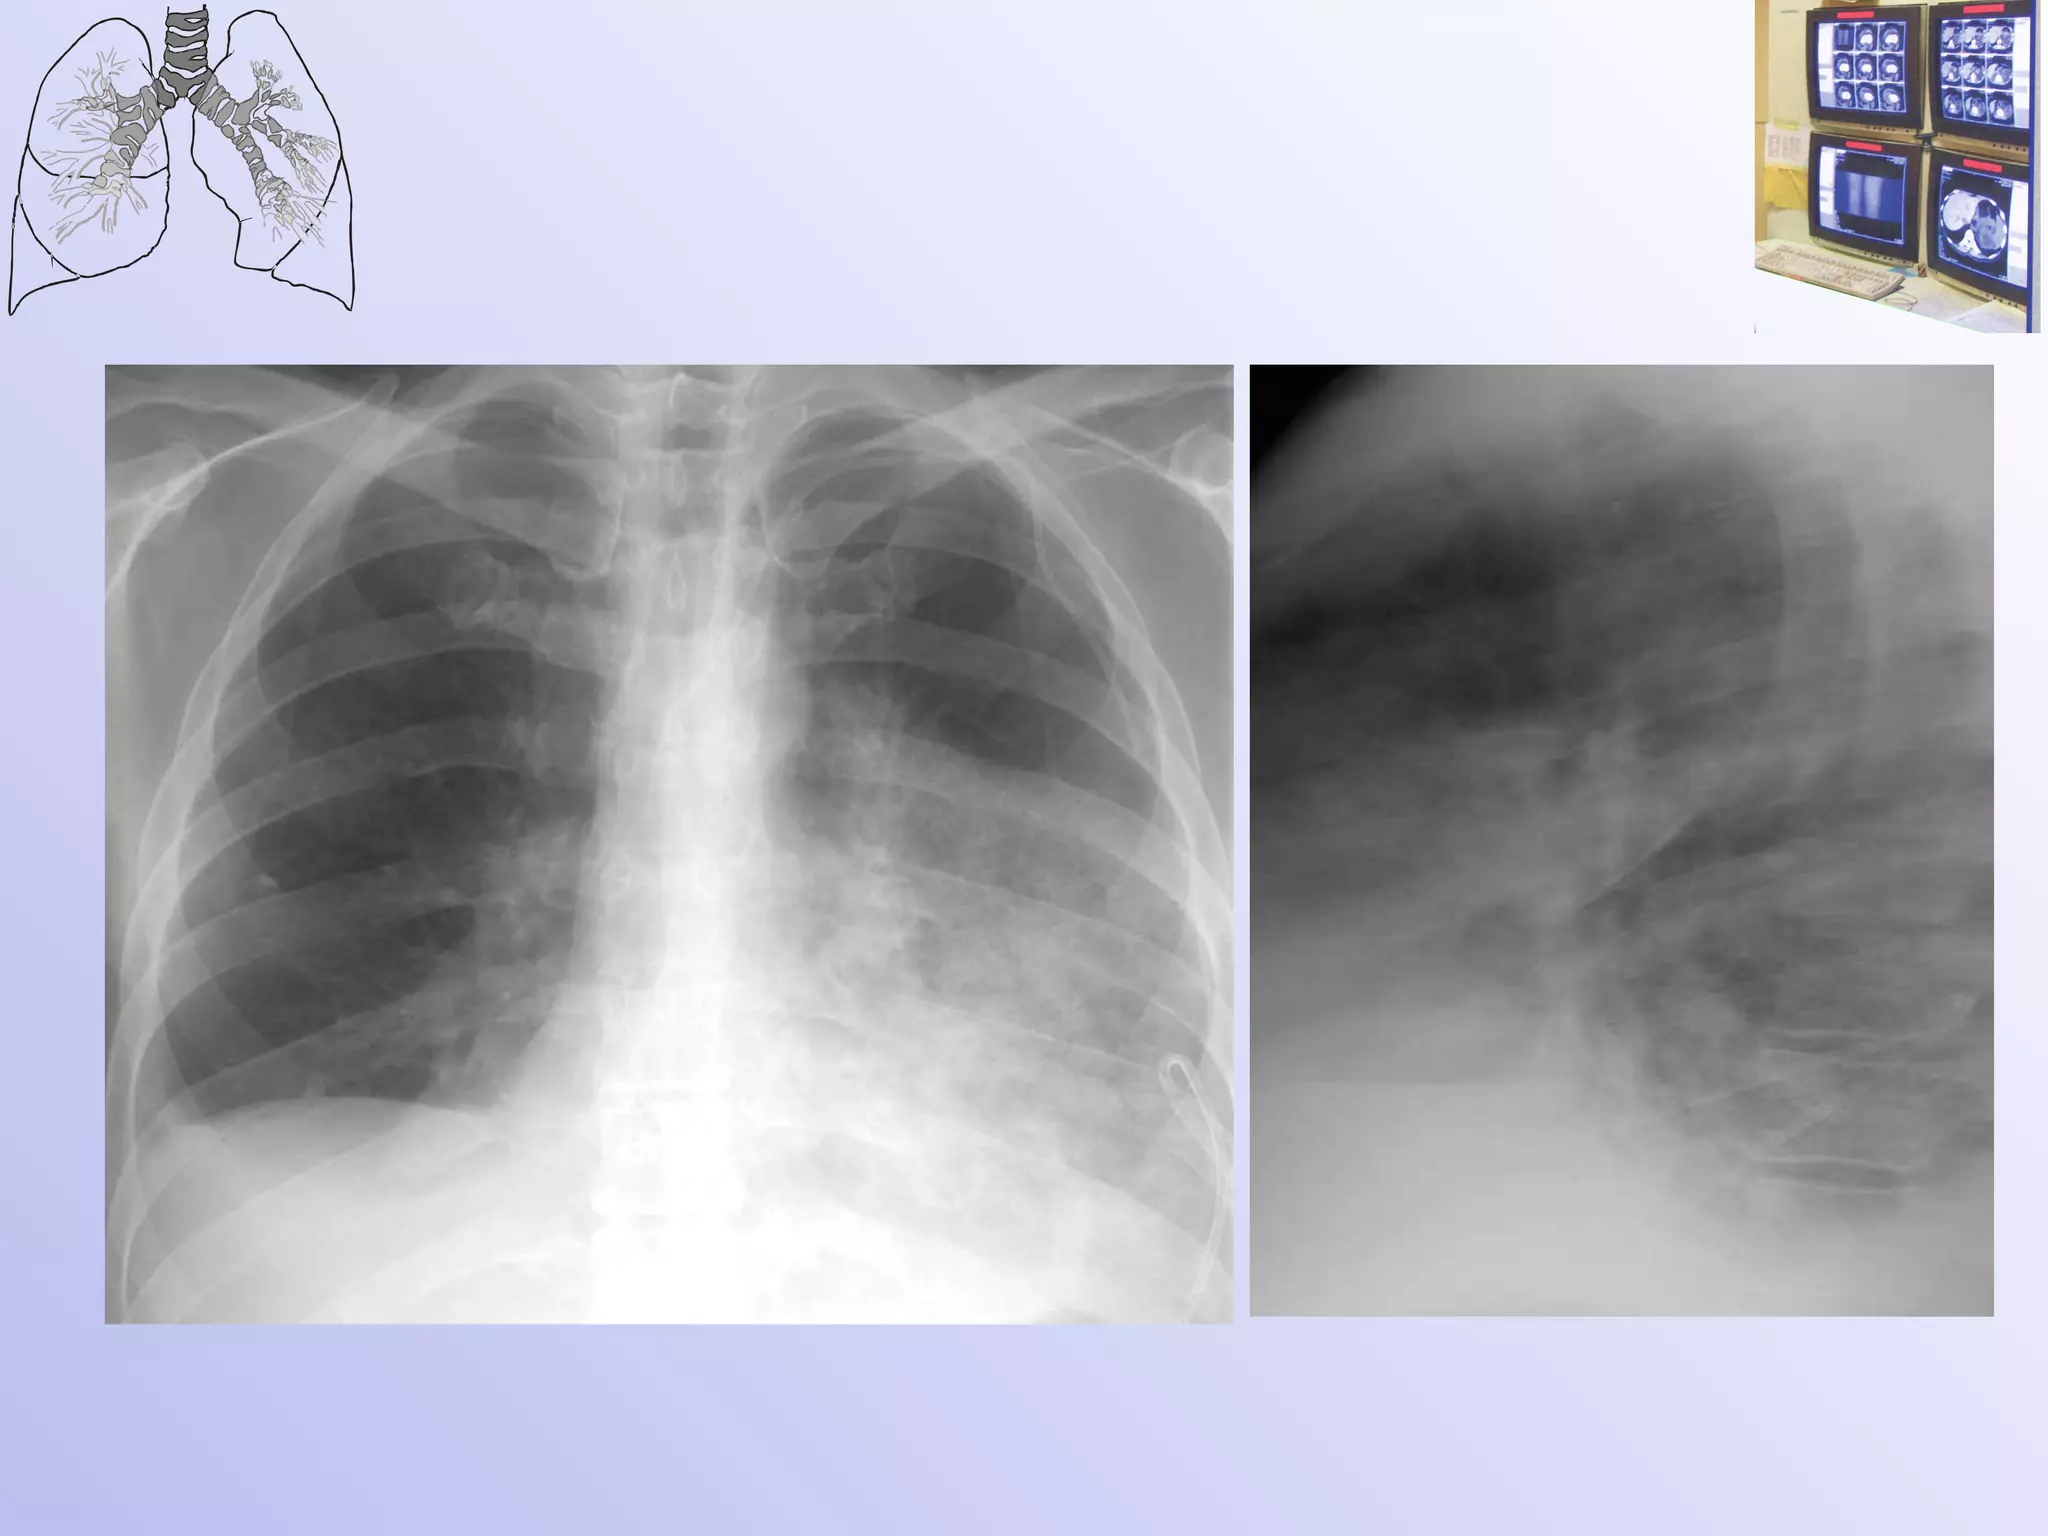

Ателектаз? Плеврит?

После пункции